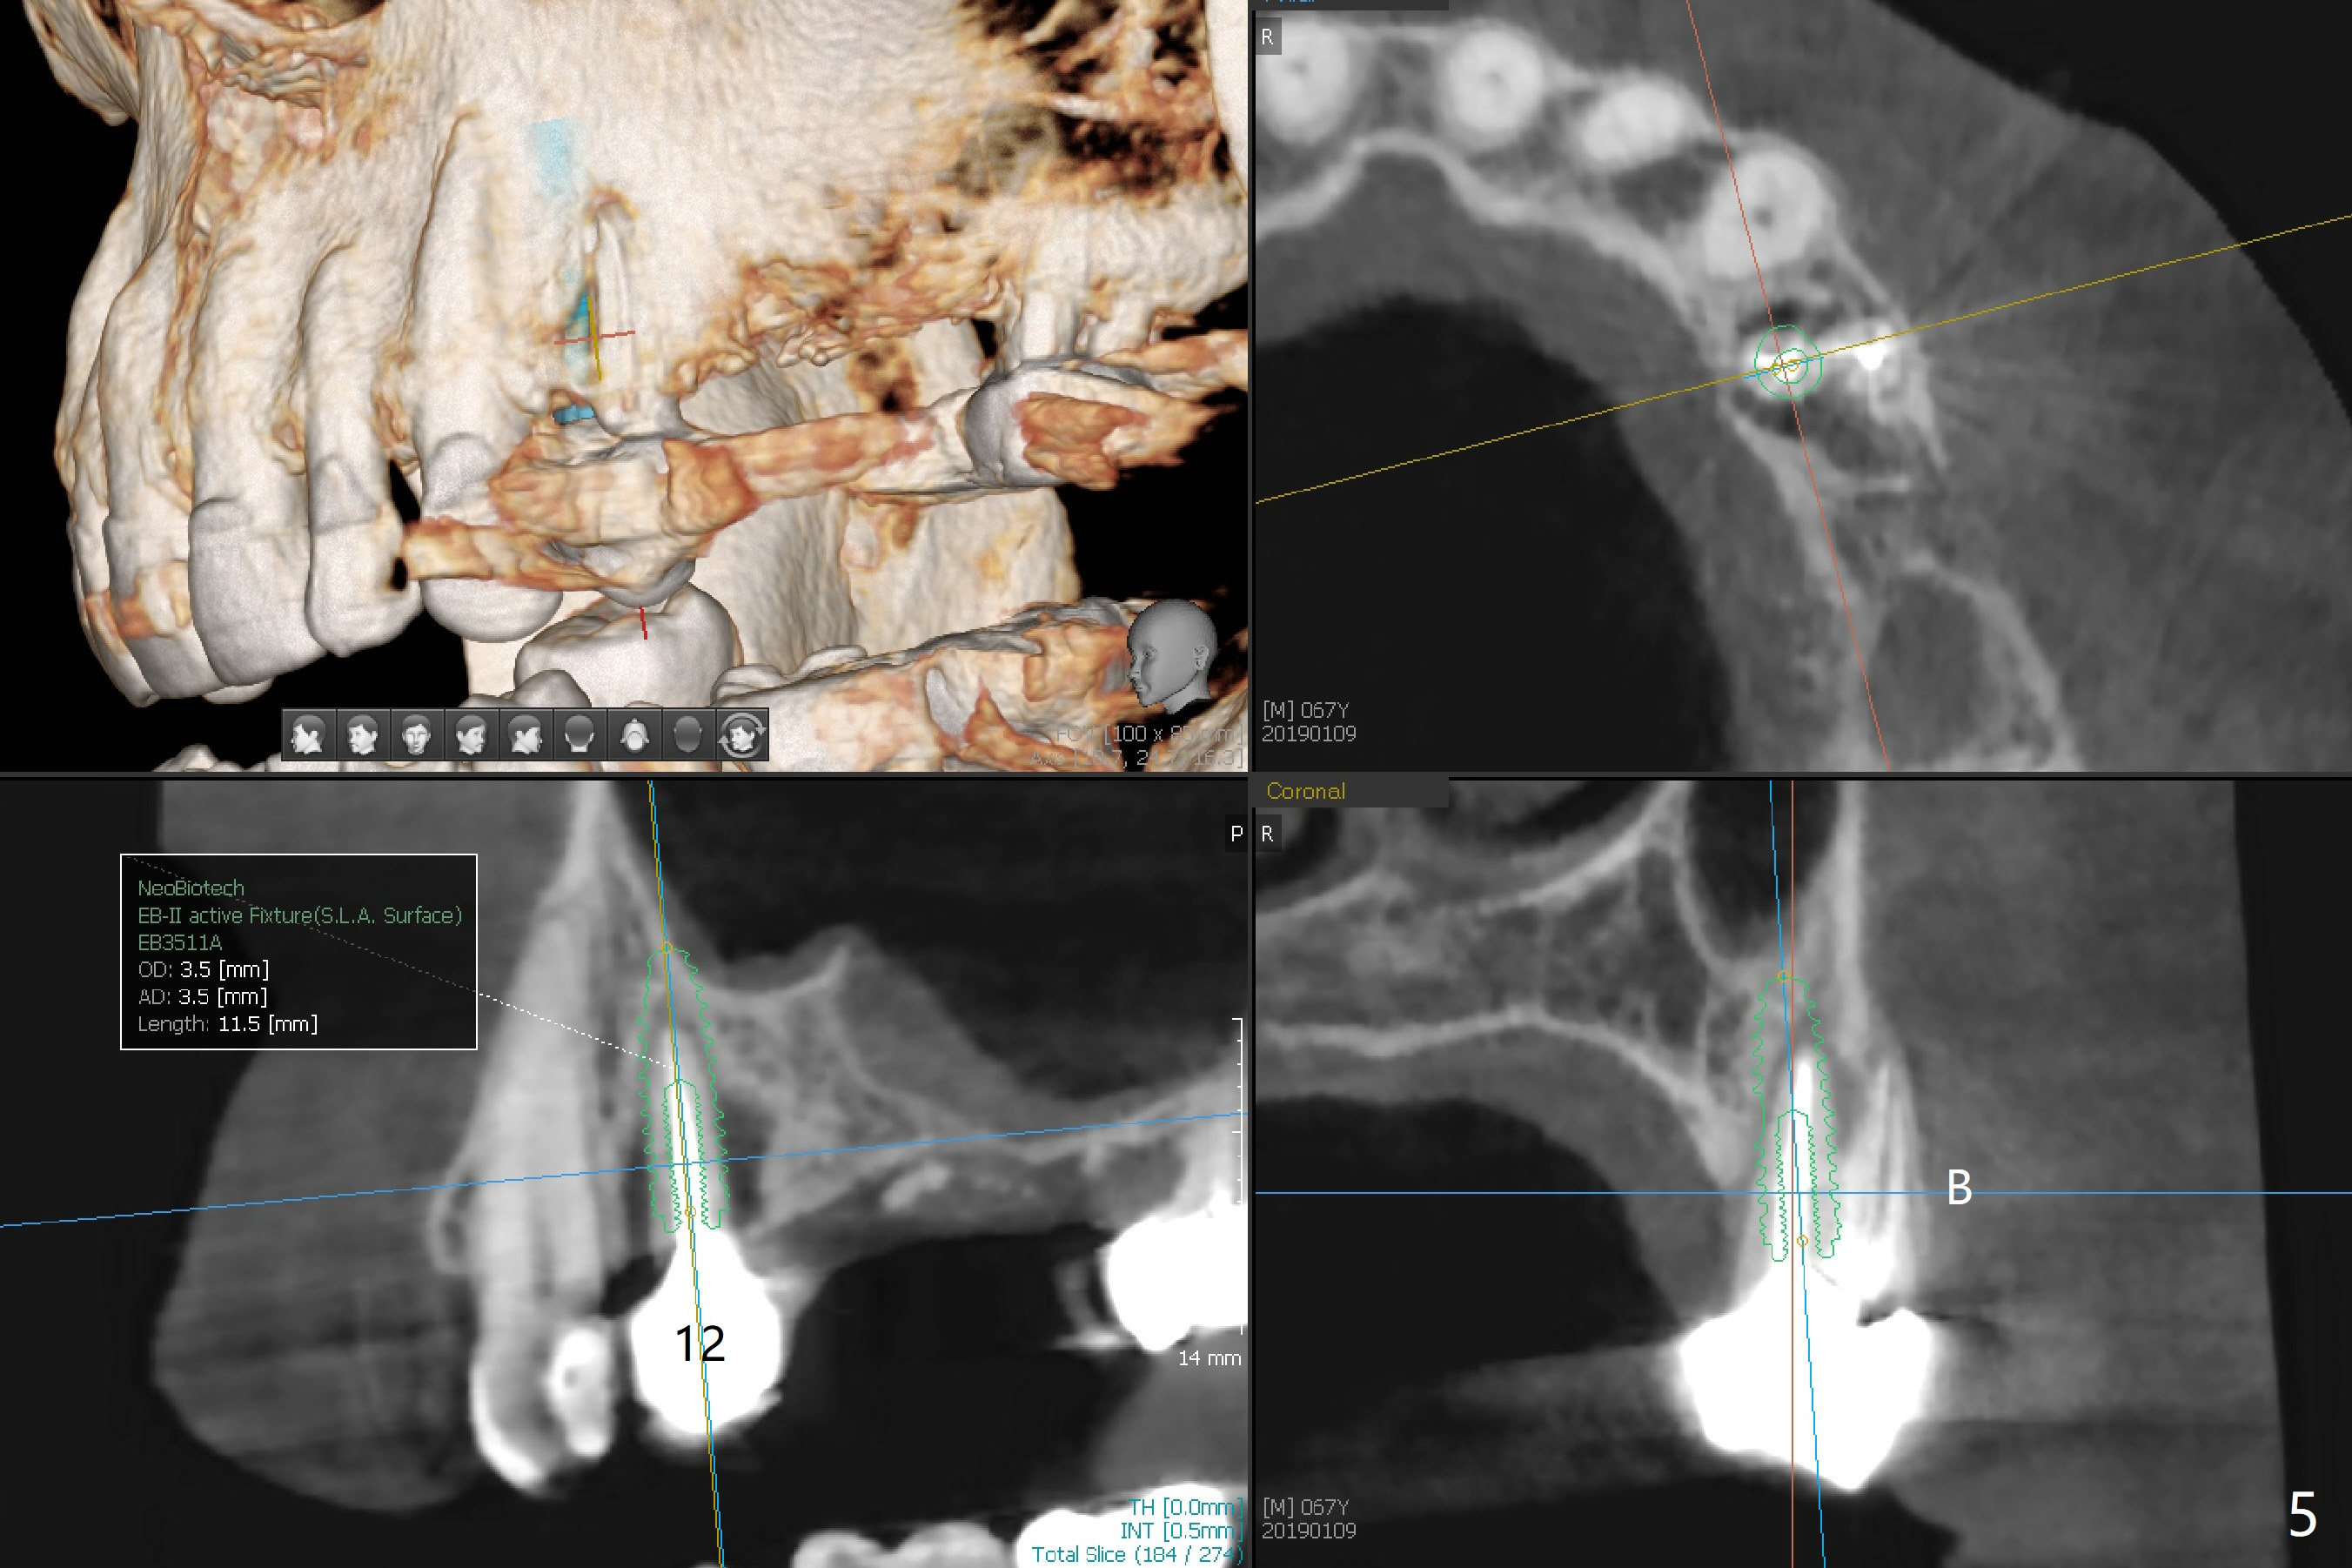

A 63-year-old woman wants to change upper RPD (for #2-4, 13 and 14) to implants because of denture-associated candidiasis. She is afraid of osteoporosis, although the implant at #18 is doing fine almost 3 months post cementation (Fig.1). One way to restore the upper right quadrant is to place 3 short implants (7.3 or 8.5 mm) with guide with simultaneous internal or external sinus lift (Fig.2-4). The tooth #12 appears to have root fracture with periradicular radiolucency (Fig.5); an immediate implant will be placed. While a short implant will be placed at #13, no implant will be placed at #14 because of 1 mm bone (Fig.6). A cantilever FPD will be fabricated in the upper left quadrant. The thick left sinus membrane is a problem as related to a lift?